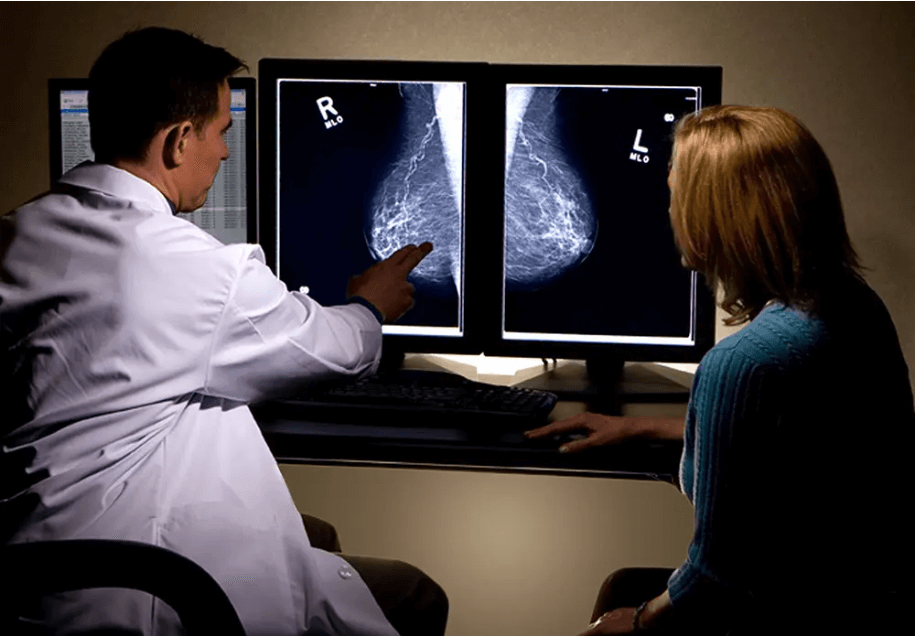

乳腺癌的“危险信号”有哪些?

1、乳房出现肿块:肿块常常是无痛的,不规则形状、单个,肿块为实性,比较硬,活动度比较差。乳腺癌的好发部位是乳房的外上象限位置 2、乳房局部皮肤出现改变:乳房的皮肤出现“酒窝征”的变化,就需要提高警惕了。 3.乳头改变:当乳腺癌的病灶侵袭到乳头或是乳晕下区域时候,乳腺的纤维组织和导管系统就可能会以为肿瘤的侵犯出现缩短的症状。然后牵拉乳头,就会使得乳头偏向肿瘤的那一侧。 如果进一步的发展,可能会出现乳头扁平、凹陷、回缩甚至是完全的缩到乳晕下面,看不到乳头。4、乳头溢液:当乳腺导管上皮出现增生、炎症、出血或是坏死、肿瘤病变的时候就可能会出现乳头溢液。 乳头溢液可能会是无色的但也可能是有颜色的如乳白色、淡黄色,重一点的颜色可能会是棕色。呈现出水样、浆液性、脓性或是血样。5、疼痛:会有隐痛或者是刺痛的症状出现。……[详情]

乳腺癌的早期症状有哪些?